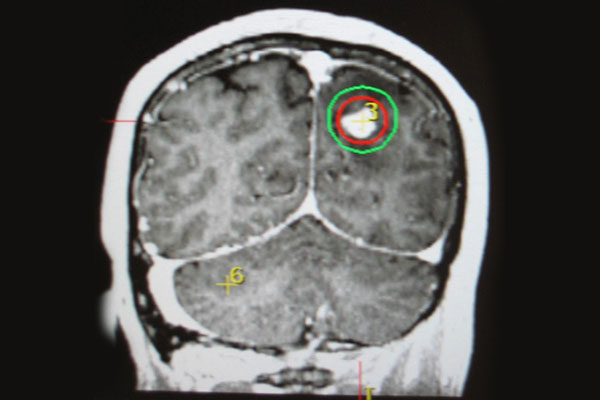

立體定位放射手術或治療 ❯